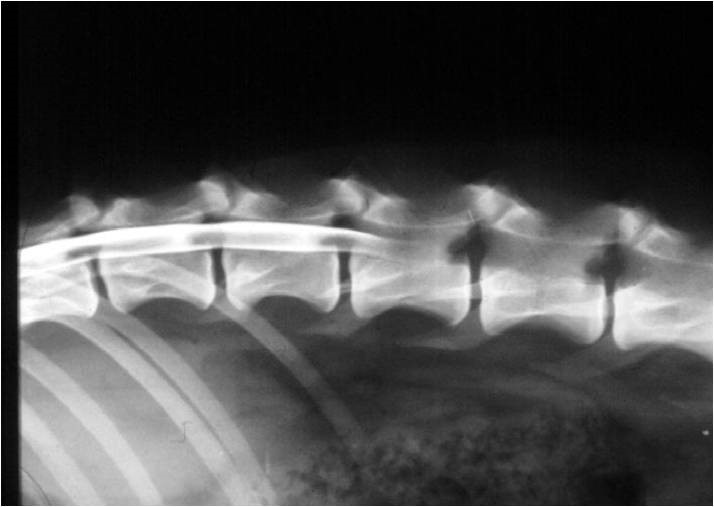

Lumbalis kontraszt stop és

dorsalis szűkület a gerinc csatornában